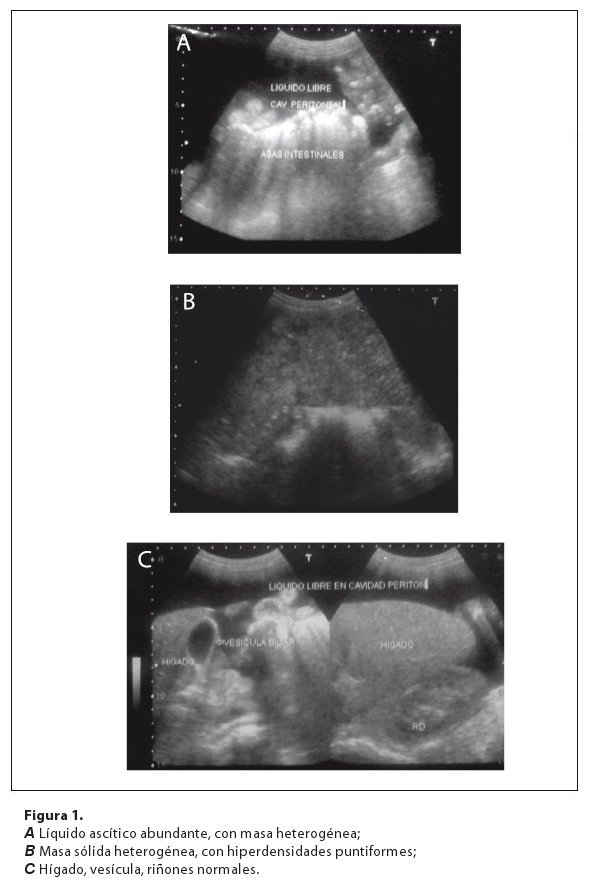

Se realiza ecografía abdominal que reporta: útero con morfología poco desplazada, no pudiéndose delimitar los ovarios, líquido ascítico abundante (fig. 1.A). Se observa ocupando casi toda la cavidad pélvica y parte de abdomen una gran masa sólida hipodensa heterogénea con múltiples hiperdensidades puntiformes diseminadas sugerentes de microcalcificaciones (fig. 1.B); de contornos mal definidos, que desplaza asas intestinales hacia arriba, de 20 x 16 x 10 cm, dependiente de anexos. Regiones isquio rectales libres, órganos abdominales normales (fig. 1.C). La conclusión del reporte ecográfico fué masa sólida en pelvis.

El estudio ultrasonográfico, es el método de elección para evaluar las masas anexiales; sugiriendo malignidad la presencia de septos mayores de 1 cm, papilas sólidas que crecen hacia adentro a expensas de la pared interna, irregularidad de los contornos, textura compleja con elementos líquidos y sólidos8, bilateralidad de las masas3, tamaño mayores a 10 cm en premenopáusicas y 5 cm en postmenopáusicas2. Hallazgos encontrados que apoyaron la naturaleza maligna en la paciente (ascitis y masa heterogénea dependiente de anexos de contornos irregulares de 20 x 16 cm), no realizándose estudio DOPPLER (vasos de neoformación), ni TAC y RMN que permiten valorar la extensión de la neoplasia.